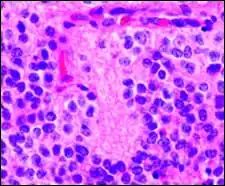

Микроскопический вид типичной нейробластомы с образованием розеток

Гистопатологический образец нейробластомы с розетками Гомера Райта, окраска гематоксилин-эозин